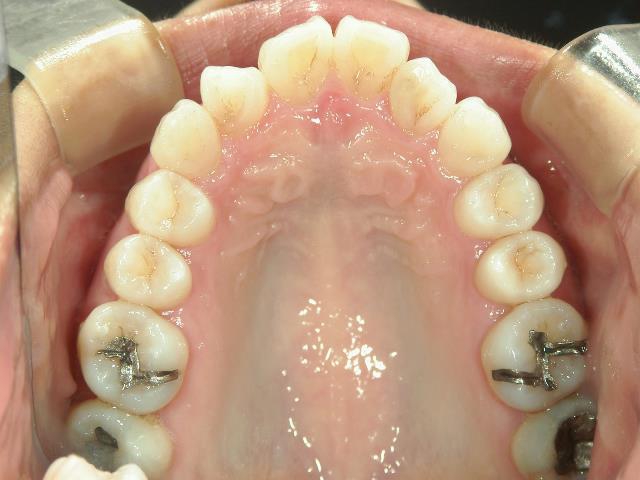

矯正歯科 治療前矯正歯科 治療前

矯正_灰色.pngno.41_ 8994_治療前_上.JPG矯正_灰色.png